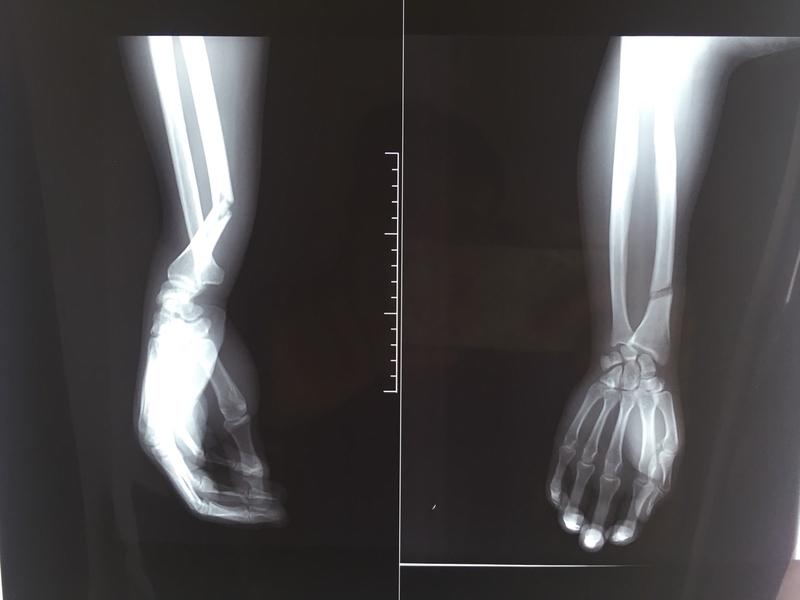

Cách sơ cứu gãy xương cẳng tay hiệu quả

Gãy xương cẳng tay là cụm từ để chỉ vị trí gãy xương nằm ở đoạn thân xương cẳng tay, tính từ dưới nếp gấp khuỷu 2cm và trên nếp gấp cổ tay 5cm. Gãy xương cẳng tay là chấn thương không ảnh hưởng trực tiếp tới tính mạng của người bệnh nhưng có thể để lại những biến chứng nặng nề và di chứng vĩnh viễn cho đôi tay. Vì vậy, sơ cứu gãy xương cẳng tay là bước đầu vô cùng quan trọng giúp phòng tránh những di chứng đó.

Gãy xương cẳng tay dùng để chỉ tình trạng xương bị gãy ở đoạn thân xương có màng gian cốt bám, nghĩa là vào khoảng 2cm dưới mấu nhị đầu của xương quay (vị trí nếp gấp khuỷu) và trên nếp gấp cổ tay 5cm. Hai xương chính thuộc vùng cẳng tay là xương quay và xương trụ, với các loại tổn thương thường gặp sau:

Cách sơ cứu gãy xương cẳng tay 1 Giới hạn gãy thân xương cẳng tay